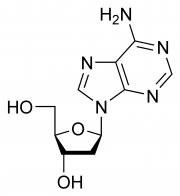

| 2021年7月26日 (一) 18:22 | DA chemical structure.png (文件) |  |

12 KB | 77921020 | Uploaded with SimpleBatchUpload | 1 |